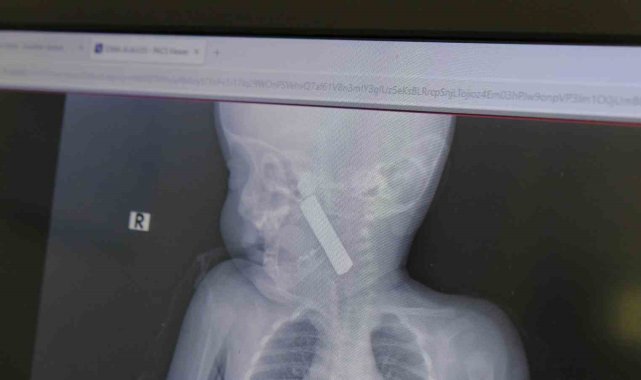

Karaman'da 6 aylık bebeğin boğazına kaçan kumanda pili, ameliyatla çıkarıldı.Edinilen bilgiye göre, kusma şikayeti ile ailesi tarafından Karaman Eğitim ve Araştırma Hastanesi acil servisine getirilen 6 aylık E.A. isimli kız bebeğin, yapılan muayene ve tetkiklerde boğazında kumanda pili kaçtığı tespit edildi. Solunum sıkıntısı da yaşayan bebek hemen ameliyata alındı. Çocuk Cerrahisi Uzmanı Doç. Dr. Mehmet Uysal tarafından yapılan ameliyatla bebeğin boğazındaki pil çıkarıldı."Hemen müdahale ettik"Yaşanan olayla ilgili bilgi veren Doç. Dr. Mehmet Uysal, "Acil polikliniğimize kusma şikayeti ile 6 aylık bir kız bebek getirilmiş ve bize haber verildi. Biz de vakit kaybetmeden geldik, hastamızı gördük. Yapılan tetkikler sonucunda, ağız tabanına oturan ve yemek borusunun birinci darlığına kadar uzanan, kumanda pili dediğimiz bir pille karşılaştık. Filmde ve muayenede bunu gördük. Hastayı ilk gördüğümüzde bayağı siyanotik durumda, solunum sıkıntılıydı ve oksijen satürasyonu 90 civarındaydı. Böyle olunca bir an önce beklemeden hızlı bir şekilde ameliyathaneye götürdük. Orada ameliyathanedeki anestezi uzmanlarımız ve personel bize yardımcı oldu, hasta hızlı bir şekilde entübe edildi. Ondan sonra da laringoskop ve magill forseps dediğimiz malzemelerimizle bu yabancı cismi çıkarmış olduk. Bir an evvel müdahale ettik, iyi ki müdahale ettik, orada ağız tabanında, özellikle ön kısmında hasar oluşmuştu. Müdahale sonrasında da hastanın solunum problemleri bir süre devam etti, bu yüzden 24 saat takip ettik. Herhangi bir problem oluşmayınca 24 saat sonra kontrole gelmek üzere hastayı taburcu ettik" diye konuştu."Aileleri uyarıyoruz"Ailelere uyarılarda bulunan Doç. Dr. Uysal, "Bu konularda aileleri uyarıyoruz. 1 yaş altı çocuklarda bile bu durum oluşabilir. Bazen 2-3 yaş diyoruz ama 1 yaş altındaki çocuklarda da emekleme döneminde bile bu tür yabancı cisimleri, özellikle kumanda pili, kalem pil gibi şeyleri ortada bırakmamak lazım. Çocuklar meraklı olduğu için her şeyi ağzına götürmeye meyilli. Dikkat etmediğimiz takdirde ölümcül sonuçlar oluşabiliyor. Bu vakada şanslıydık, çocuktaki durum erken fark edildi ve hemen müdahale edildi. Şu anda çocuk sağlıklı bir şekilde hayatına devam ediyor" dedi.